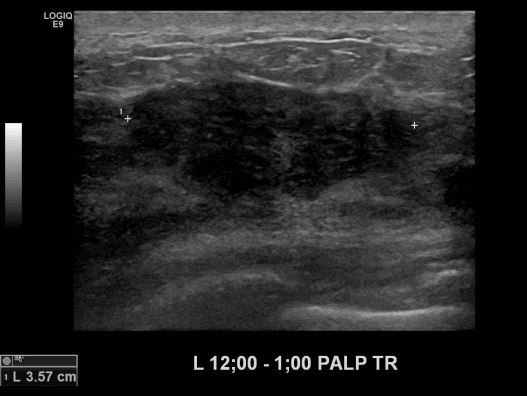

상기환자 겨드랑이에 만져지는 멍울로 내원하신 40대 여성분으로 본원 초음파상

좌측 유방 12시에서 1시 방향 만져지는 멍울 조직검사 시행하여 좌측 침윤성 유관암

진단되었습니다.